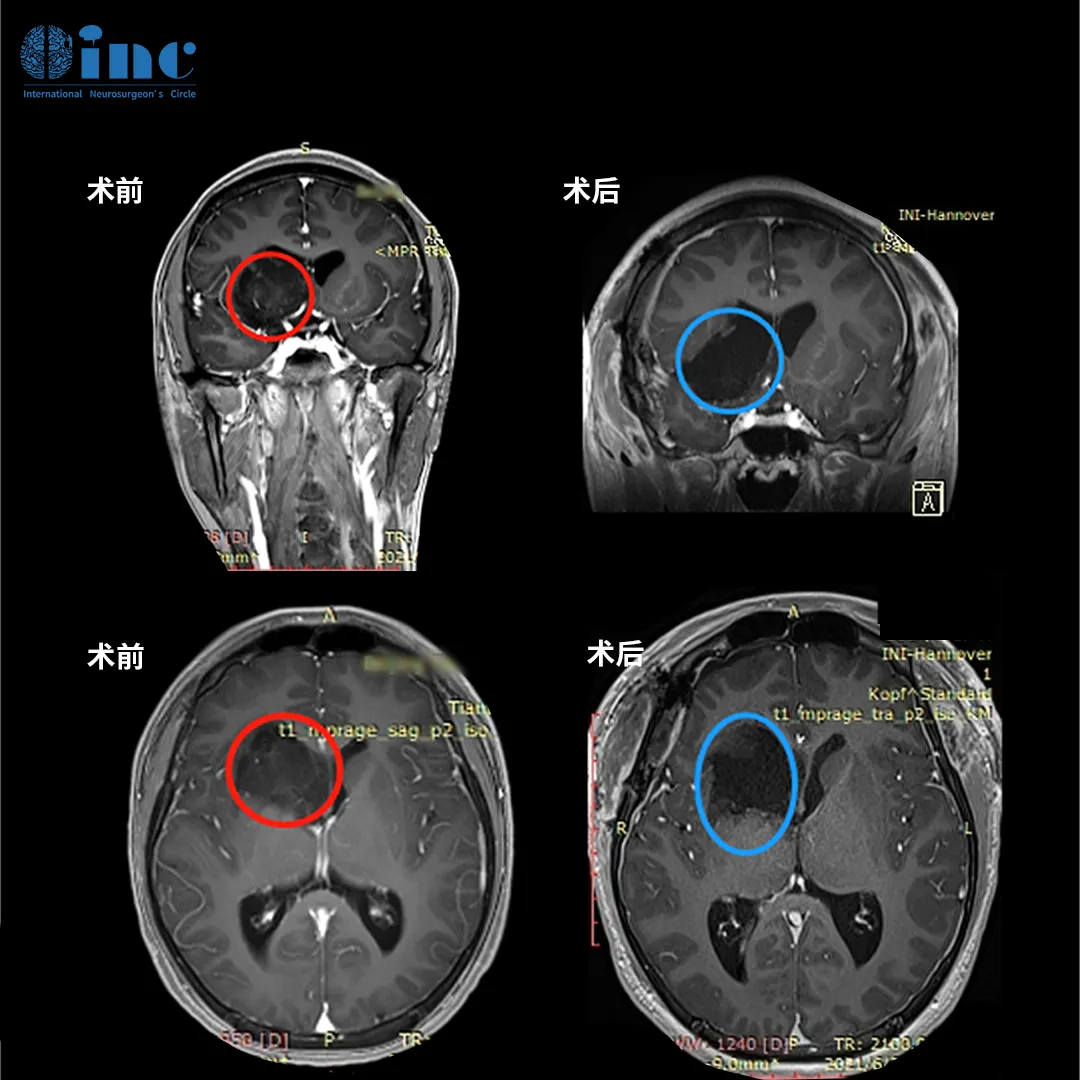

小磊术前MRI影像显示右额、颞、基底节区、侧脑室前角区占位

术前术后MR磁共振对比,术前右额、颞、基底节区、侧脑室前角区较大占位,压迫岛叶及脑室,脑室增大。术后MR提示肿瘤近全切,占位效应解除,无新发脑损伤等。

▼术前术后影像资料:

图:术前MR显示岛叶占位,直径约为4 cm,紧邻重要脑功能区,包绕左岛叶的大部分,并在背侧延伸至岛叶的后部。术后MR显示肿瘤全切,无脑出血、水肿等正常脑组织损伤。